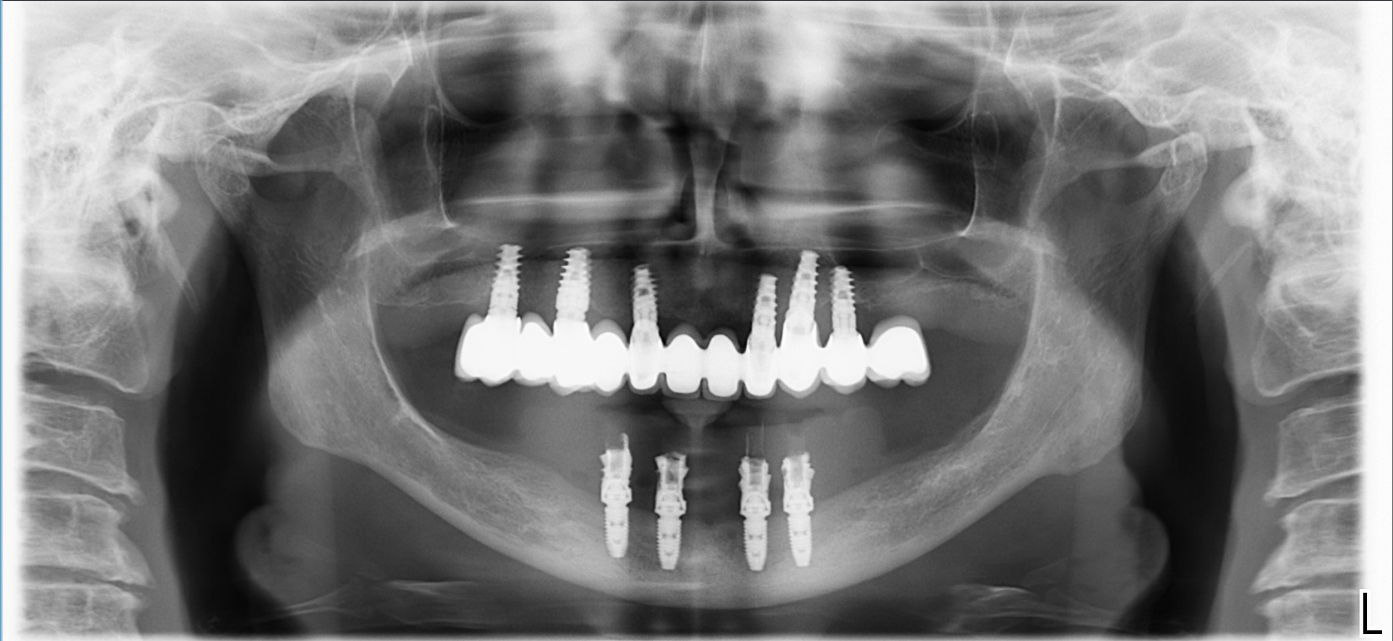

Ovviamente l’intervento è andato alla grande. In poche ore la paziente ha avuto i suoi “nuovi denti fissi” provvisori, dopo un intervento di una quarantina di minuti.

Dopo tre mesi l’ho rivista per le impronte definitive e dopo la prova di ieri tra due settimane andremo in consegna con il definitivo.